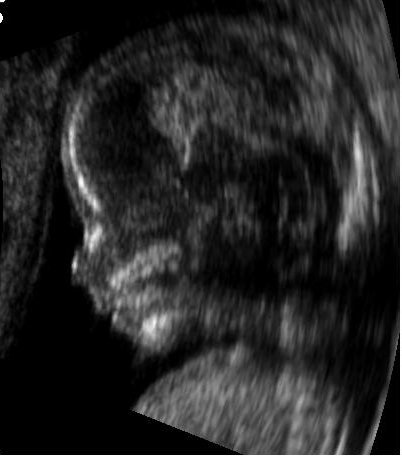

英國團隊結合核磁共振技術,透過嬰兒的心跳狀態,投射成清楚的3D成像。(photo by 網路截圖)

【台灣醒報記者宋秉謙綜合報導】核磁共振轉化成3D圖像,新科技讓醫生能判讀由在子宮內的嬰兒狀態,有助於及早發現先天性疾病。英國公衛局(NHS)日前表示,學界開發出高強度計算機程序,能透過核磁共振,將嬰兒的心跳與運動狀態轉成清晰3D圖像,讓醫生能針對有先天性疾病嬰兒做出診斷治療。

根據《天空新聞網》報導,英國公衛局日前發表學界新成果,利用特殊的計算機程序,把過往清晰度極差的三維圖片改善,並結合定期實施的核磁共振(MRI),利用嬰兒的心跳與運動狀態變化,轉成清晰且全面的3D圖像,以便醫生判讀,有助於找到新生兒的先天性疾病。

科學家舉出研究中一例臨床實測,該例中的新生兒是在其母親懷孕20週時,進行MRI的超聲波而發現問題,圖中清楚顯示女嬰的主動脈變窄,出生後高機率會罹患血塞,所幸有這項技術,在動完心臟手術後,到現在已是11個月大的健康女嬰。